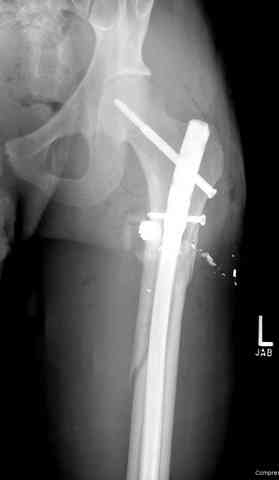

Здесь представлены несколько случаев лечения огнестрельного перелома

1 Проксимальный перелом бедра, антеградный гвоздь

Для фиксации огнестрельных переломов бедра и длинных костей предпочтение отдаем интрамедуллярному методу фиксации, о котором еще в 1993 году написали Bergman M. Tornetta P. Kerina M. Sandhu H. Simon G. Deysine G. Journal of Trauma. [JC:kaf] 34(6):783-5